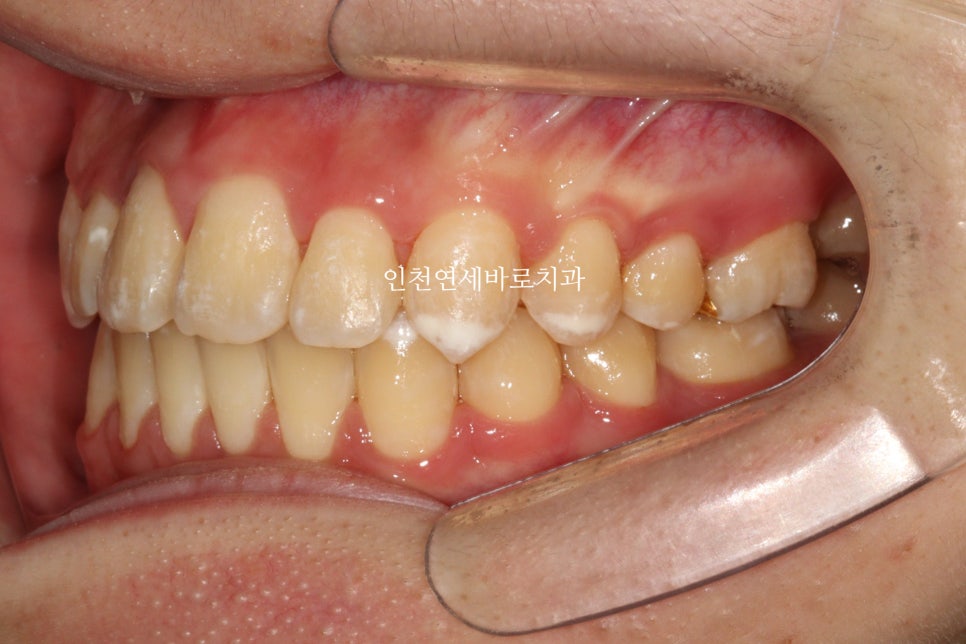

위와 같이 삐뚤삐뚤했던 치열을 가진 아이가 와서 #철사교정 치료를 하고

마무리가 되었습니다.

스마일이 훨씬 자연스러워져 보입니다.